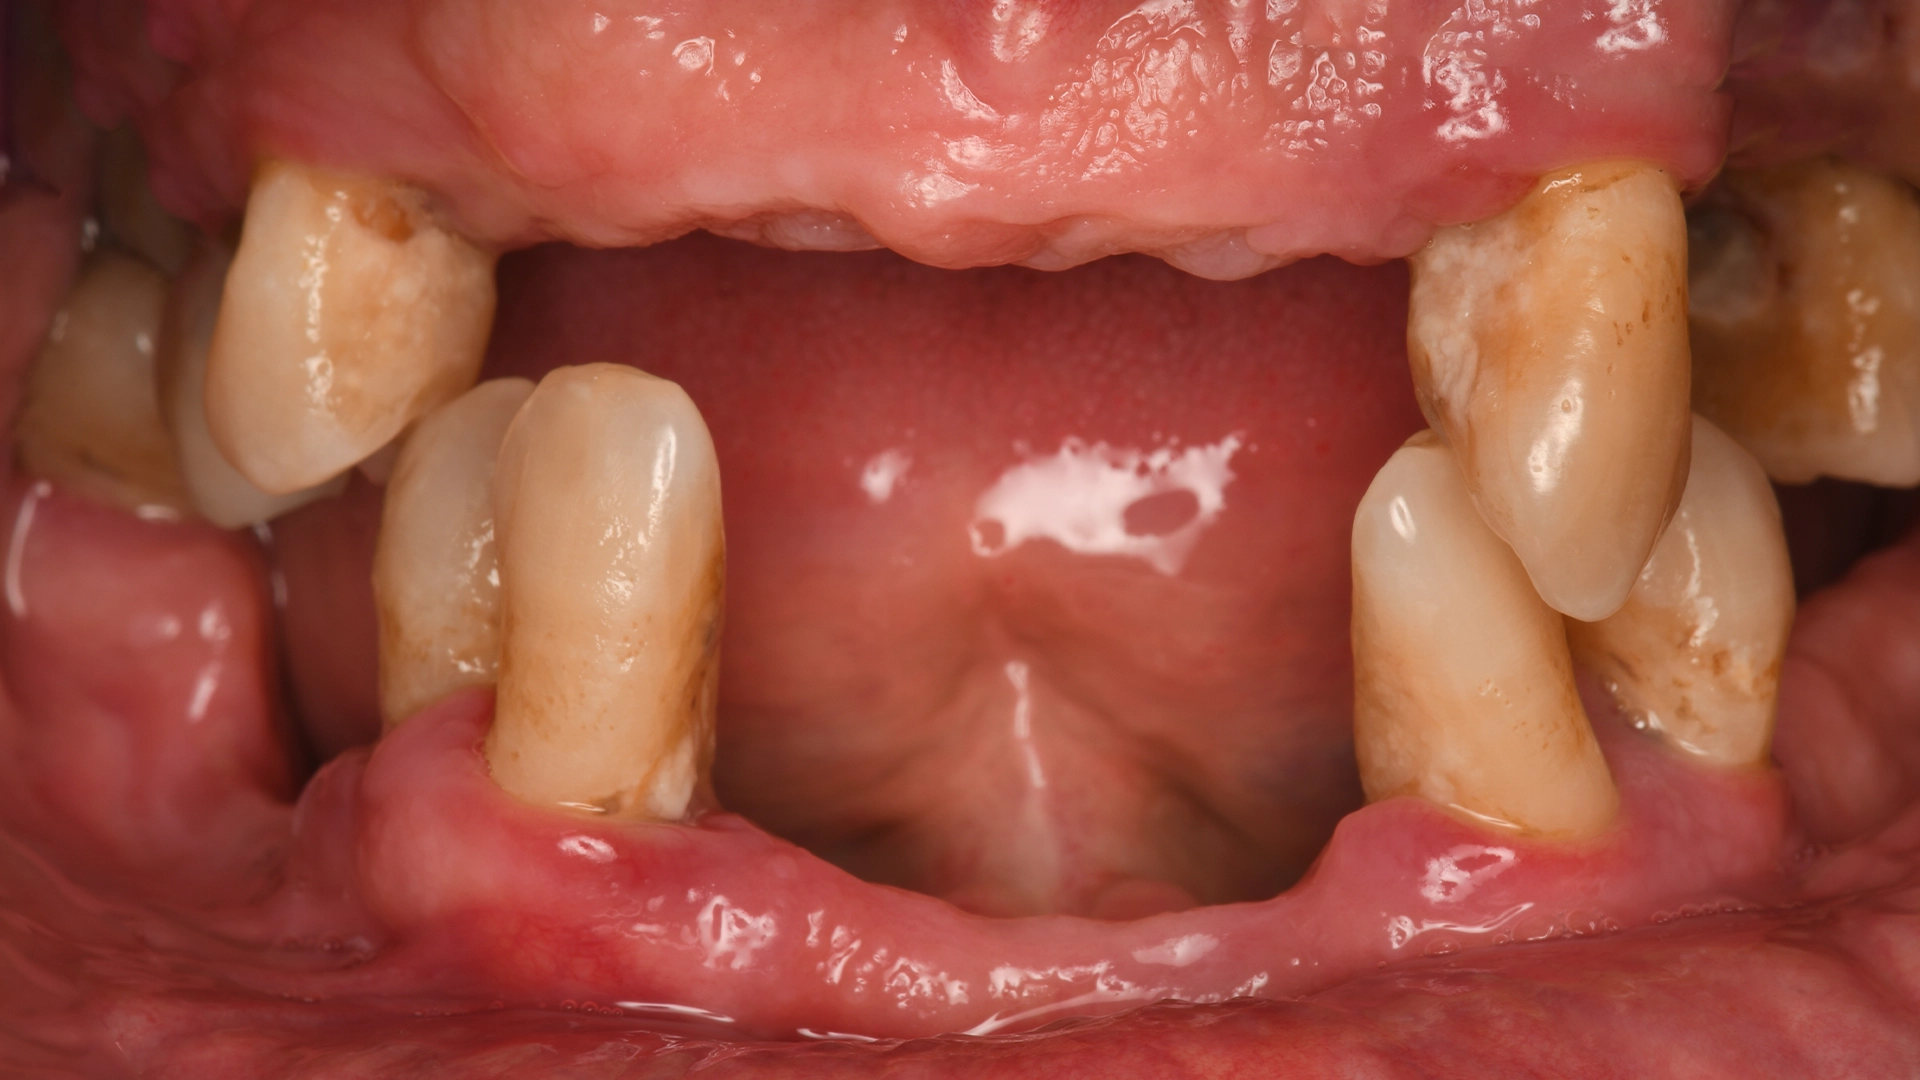

If you’re reading this, you’ve probably been living with a missing tooth—or several—for longer than you originally expected. You may have received different opinions from different dentists. You may be unsure what implant treatment actually involves, how long it takes, or whether the final result will truly feel like your own teeth.

We begin with a clinical examination and a 3D cone‑beam CT scan. This scan allows us to assess the exact bone volume and density at the implant site, identify the position of nerves and sinuses, and determine whether any preparatory procedures are required.

If bone grafting is required, we explain why, what it involves, and how it affects timing.

Delaying replacement can lead to: